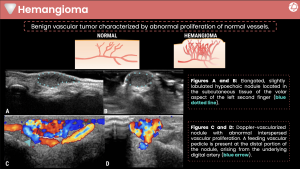

Hemangiomas

Hemangiomas are benign vascular tumors characterized by abnormal proliferation of blood vessels. They may present at any age and commonly manifest as soft, compressible masses that may increase in size with dependency or Valsalva maneuver. Pain or functional limitation may occur depending on size and location.

Ultrasound typically demonstrates a hypoechoic or heterogeneous, lobulated soft-tissue mass located in the subcutaneous tissues. Color and power Doppler reveal prominent internal vascularity, often with low-resistance arterial flow and, in some cases, identifiable feeding vessels arising from digital arteries. Phleboliths, when present, appear as echogenic foci with posterior shadowing.